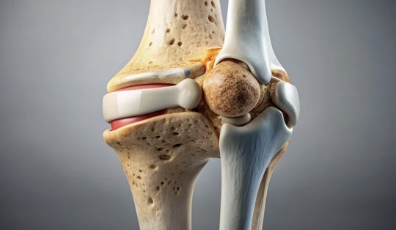

무릎 연골은 뼈와 뼈 사이에서 완충 작용을 하여 관절의 부드러운 움직임을 돕고, 마찰을 줄여주는 역할을 해요.

- 연골의 종류: 무릎에는 반월상 연골과 관절 연골, 두 가지 종류의 연골이 있어요. 반월상 연골은 무릎 안쪽과 바깥쪽에 C자 모양으로 위치하며, 충격 흡수와 안정성 유지에 중요한 역할을 합니다. 관절 연골은 뼈 끝 부분을 덮고 있으며, 뼈끼리 부딪히는 것을 막아주고 부드러운 움직임을 가능하게 해요.